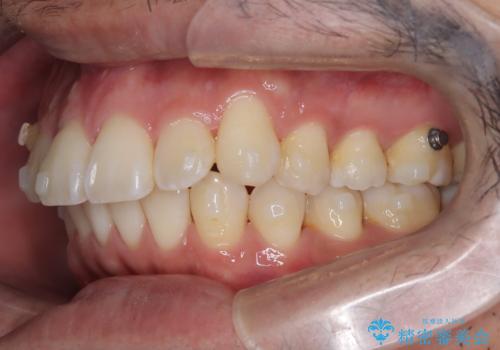

【インビザライン】前歯の凸凹を解消。

- 前歯の凸凹を主訴に来院されました。

もともと、顎が左にシフトしていたので正中が合わないことを説明した後、矯正を開始しています。

短期間で前歯のがたがたがきれいになり、満足していただけました。

顎が偏移している場合は、正中やかみ合わせは正常と比べずれた位置での仕上がりとなります。